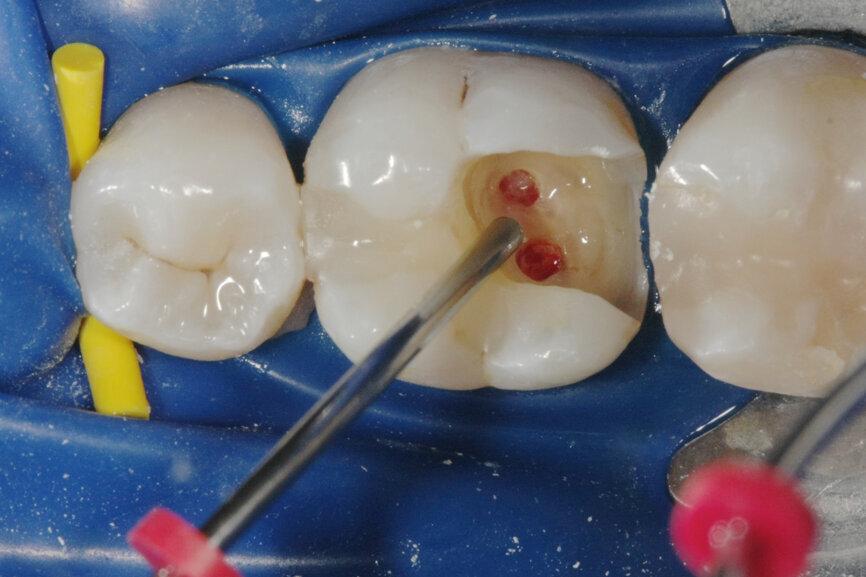

Vital pulp therapy has become more popular in recent years. Calcium hydroxide has been the most common material for pulp capping, but MTA has shown even better results in biocompatibility and outcome.[3] Cases with large carious pulp exposure can be treated successfully with partial pulpotomy and MTA as a capping agent, keeping teeth vital (Figs. 1a–e).

Fig. 1a: (a) Deep carious lesion. (b) Partial pulpotomy. (c) MTA application with the MAP System and PD MTA White. (d) Filling. (e) Post-op radiograph showing the pulp capping with MTA.

Fig. 1b: (a) Deep carious lesion. (b) Partial pulpotomy. (c) MTA application with the MAP System and PD MTA White. (d) Filling. (e) Post-op radiograph showing the pulp capping with MTA.

Fig. 1c: (a) Deep carious lesion. (b) Partial pulpotomy. (c) MTA application with the MAP System and PD MTA White. (d) Filling. (e) Post-op radiograph showing the pulp capping with MTA.

Fig. 1d: (a) Deep carious lesion. (b) Partial pulpotomy. (c) MTA application with the MAP System and PD MTA White. (d) Filling. (e) Post-op radiograph showing the pulp capping with MTA.

Fig. 1e: (a) Deep carious lesion. (b) Partial pulpotomy. (c) MTA application with the MAP System and PD MTA White. (d) Filling. (e) Post-op radiograph showing the pulp capping with MTA.